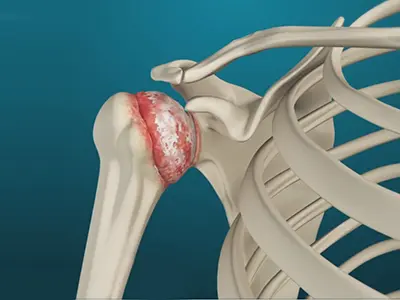

Arthritis of the Shoulder

The term arthritis literally means inflammation of a joint but is generally used to describe any condition in which there is damage to the cartilage.